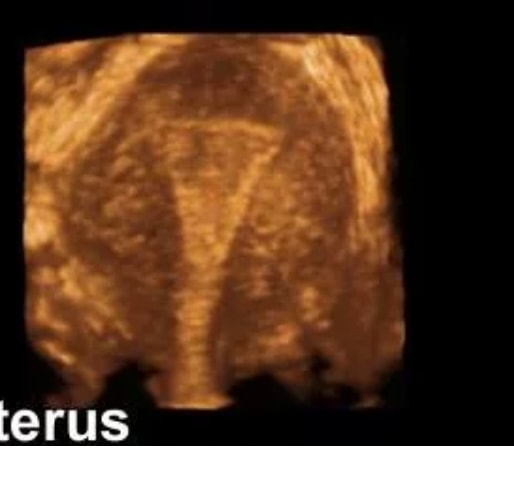

Sandra, есть картинка 3д узи матки?

вот в таком ракурсе Изображение

Наденька, да, на последнем узи делали, но с собой сейчас нет) узисты всегда говорят, что матка очень красивая🤣